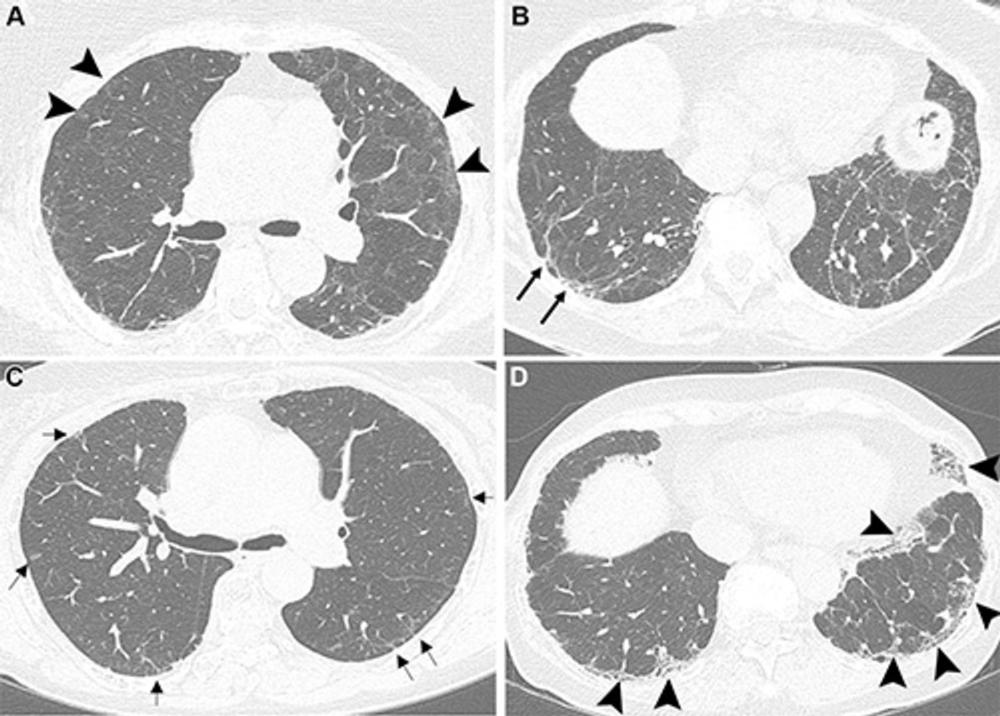

Figure 3. Unenhanced axial CT images show COVID-19 pneumonia in an 83-year-old male patient with pre-existing interstitial lung disease (ILD). (A) Image shows ground-glass opacities in the lower lobes and in the lingula (*). Irregular reticular opacities with mild distal traction bronchiectasis are evident in the subpleural regions of both upper lobes (arrowheads), suggesting pre-existing ILD with a probable usual interstitial pneumonia pattern. (B) Image obtained during hospitalization for respiratory distress shows spontaneous pneumomediastinum and diffuse chest wall subcutaneous emphysema, predominantly on the left side. The image also shows persistent, diffuse ground-glass opacities (*) and peripheral fibrotic lung changes (arrowheads). (C) Unenhanced follow-up image obtained at 6 months shows the progressive nature of lung fibrosis, with the development of honeycombing (arrowheads) and severe bronchiectasis (arrows), predominantly affecting the anterior peripheral regions of both lungs. (D) Unenhanced follow-up image obtained at 14 months shows the progression of honeycombing (arrowheads) and severe bronchiectasis (arrows) at the anterior peripheral regions of both lungs. In this case, SARS-CoV-2 infection likely acted as a trigger for the exacerbation of previously undiagnosed fibrotic ILD, with mechanical ventilation potentially contributing to extensive fibrosis in the anterior lung regions (arrowheads). The patient was administered antifibrotic therapy after the resolution of the acute phase.